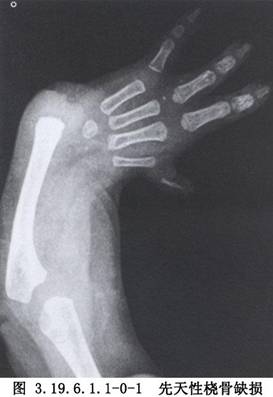

矫正桡骨缺损的腕关节成形术用于先天性桡骨缺损的手术治疗。先天性桡骨缺损又称轴旁性桡骨半肢畸形,较为多见,半数以上为双侧,单侧者以右侧居多,男性多于女性。主要临床表现为前臂短,腕关节向桡侧偏斜、不稳定,故有桡侧拐状手之称。本病除桡骨完全或部分缺损外,有时并发拇指、腕、掌诸骨发育不良或缺损及同侧尺骨弯曲粗大。可并发其他部位的畸形,前臂肌肉、肌腱、神经、血管的缺如或畸形也经常存在(图3.19.6.1.1-0-1)。